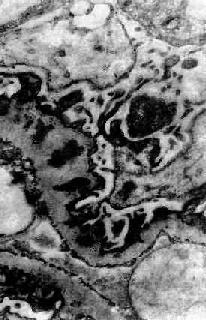

膜性肾小球肾炎

电镜下见肾小球毛细血管基底膜增厚,电子致密沉积物被增生的基底膜包围并埋藏于基底膜内